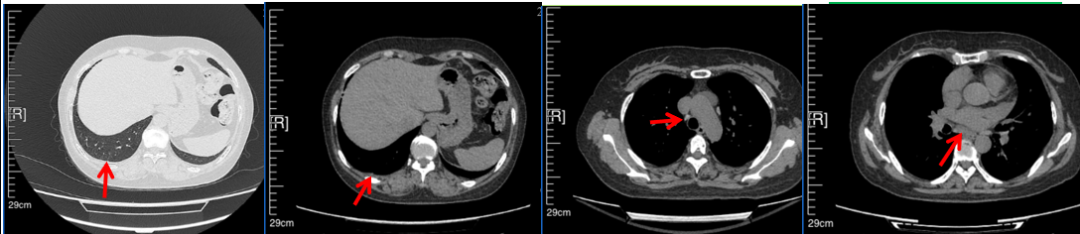

56岁,女性,无吸烟史饮酒史,既往体健。2023年02月患者体检发现肺占位性病变,胸部增强CT:右肺下叶后基底段结节;右侧锁骨上及纵隔内多发淋巴结肿大。PET-CT:右肺下叶周围型肺癌可能性大;1R、2L、3P、4R、4L及7组淋巴结转移可能性大。2023年02月就诊于本院胸外科行超声胃镜下纵隔肿物穿刺活检术,病理:结合免疫组化,符合肺腺癌。行NGS基因检测:EML4:exon20-ALK:exon20融合。PD-L1(克隆号22C3)TPS=55%。

治疗经过:2023年3月27日始行恩沙替尼靶向治疗至今,最佳疗效为PR,末次评效为维持PR。期间出现轻度肝功能异常(DILI 1级),对症处理后好转。截止目前PFS为26个月。

2023年2月20日基线检查

2024年6月复查PR(最佳疗效)

2024年12月复查维持PR

2025年3月复查维持PR